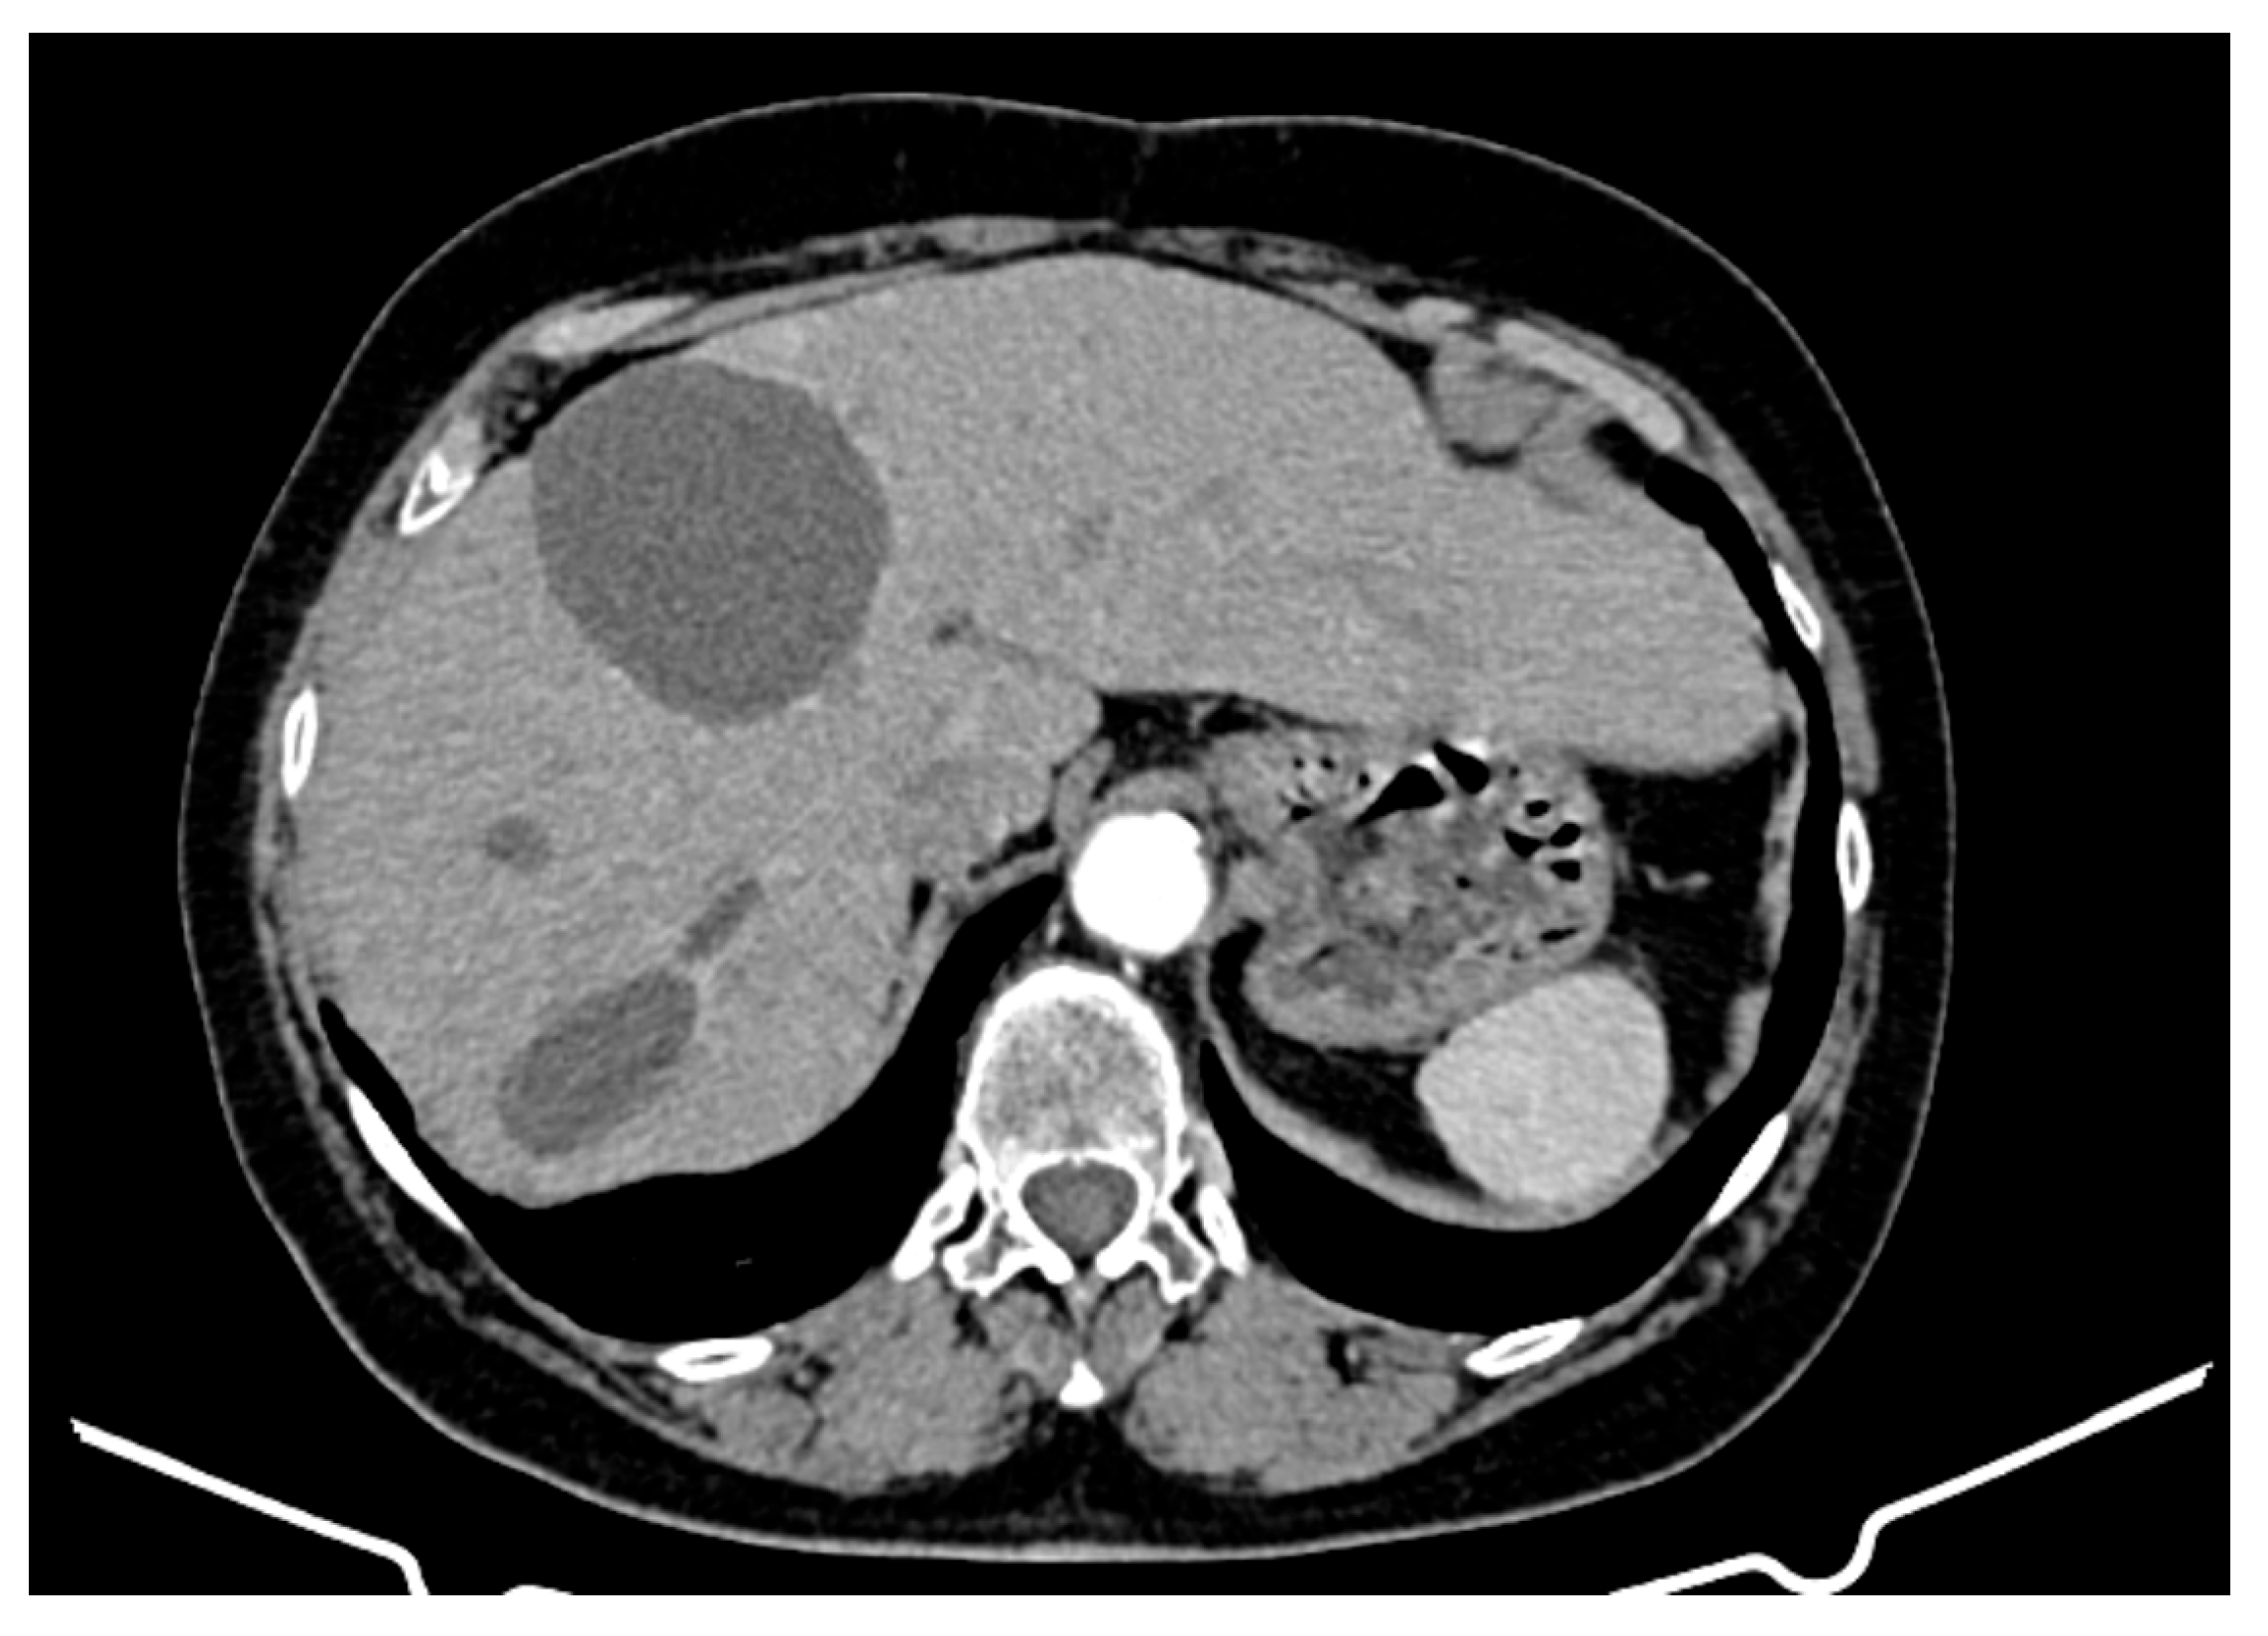

Over the course of 55 months of treatment with imatinib, the patient was monitored by imaging, exhibiting a stable disease course with no significant tumour progression and some evidence of partial regression of specific lesions. CT appearance at 12 months of treatment with imatinib is presented in Figure 3. The following key observations emerged from the serial CT evaluations:

Figure 3.

CT appearance at 12 months of treatment with imatinib at different abdominal levels.

- Hepatic tumour stability: Multiple large cystic hepatic lesions remained stable in size throughout the monitoring period, with no significant new secondary lesions developing. The largest hepatic cystic tumours persisted in segments IV, VI, and VIII, with maximum dimensions of ~8 cm, without major structural changes.

- Regression of extrahepatic lesions: Initial gastric and peritoneal lesions, including a cystic formation in the anterior gastric wall and ascitic fluid, regressed significantly by month 14 and did not reappear in later scans. The left inguinal hernia, although noted consistently, remained unchanged, without complications.

- Emergence of new findings without aggressive progression: A subcapsular nodule (3.5 × 2 cm) in Morrison’s space was identified during month 41, remaining stable without concerning enhancement patterns. A pseudo-nodular perfusion anomaly in segment VIII was noted but was attributed to pressure from the large cystic tumour rather than neoplastic progression. Mild gastric antral wall thickening developed later (by month 49), with a maximum thickness of 14 mm, but remained stable thereafter, with no associated adenopathy or signs of malignant transformation.

- Absence of significant distant metastases or new systemic involvement: Throughout the entire monitoring period, there were no newly detected secondary metastatic lesions in the thoracic, abdominal, or pelvic regions; no significant adenopathy was identified; and there was no recurrence of ascitic fluid beyond a mild amount in the early monitoring phases.